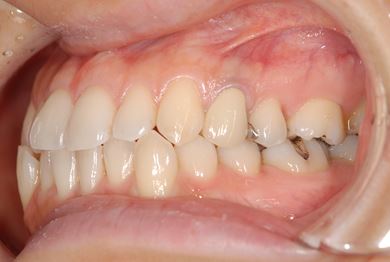

| 性別/年齢 | 女性 / 34歳 | ||||||||||||||||||||||||||||||||

| 主訴 | 以前虫歯を治療して金属を入れたところが、再び虫歯になったのか、軽くしみたり違和感がある。 | ||||||||||||||||||||||||||||||||

| 治療方針 | セラミック治療にて、審美的回復を行う。 | ||||||||||||||||||||||||||||||||

| 治療内容 | メタルボンドセラミッククラウン1本(メタルボンド用土台1本) | ||||||||||||||||||||||||||||||||

| 総治療費 | 125,685円 | ||||||||||||||||||||||||||||||||

| 治療期間 | 3ヶ月 |